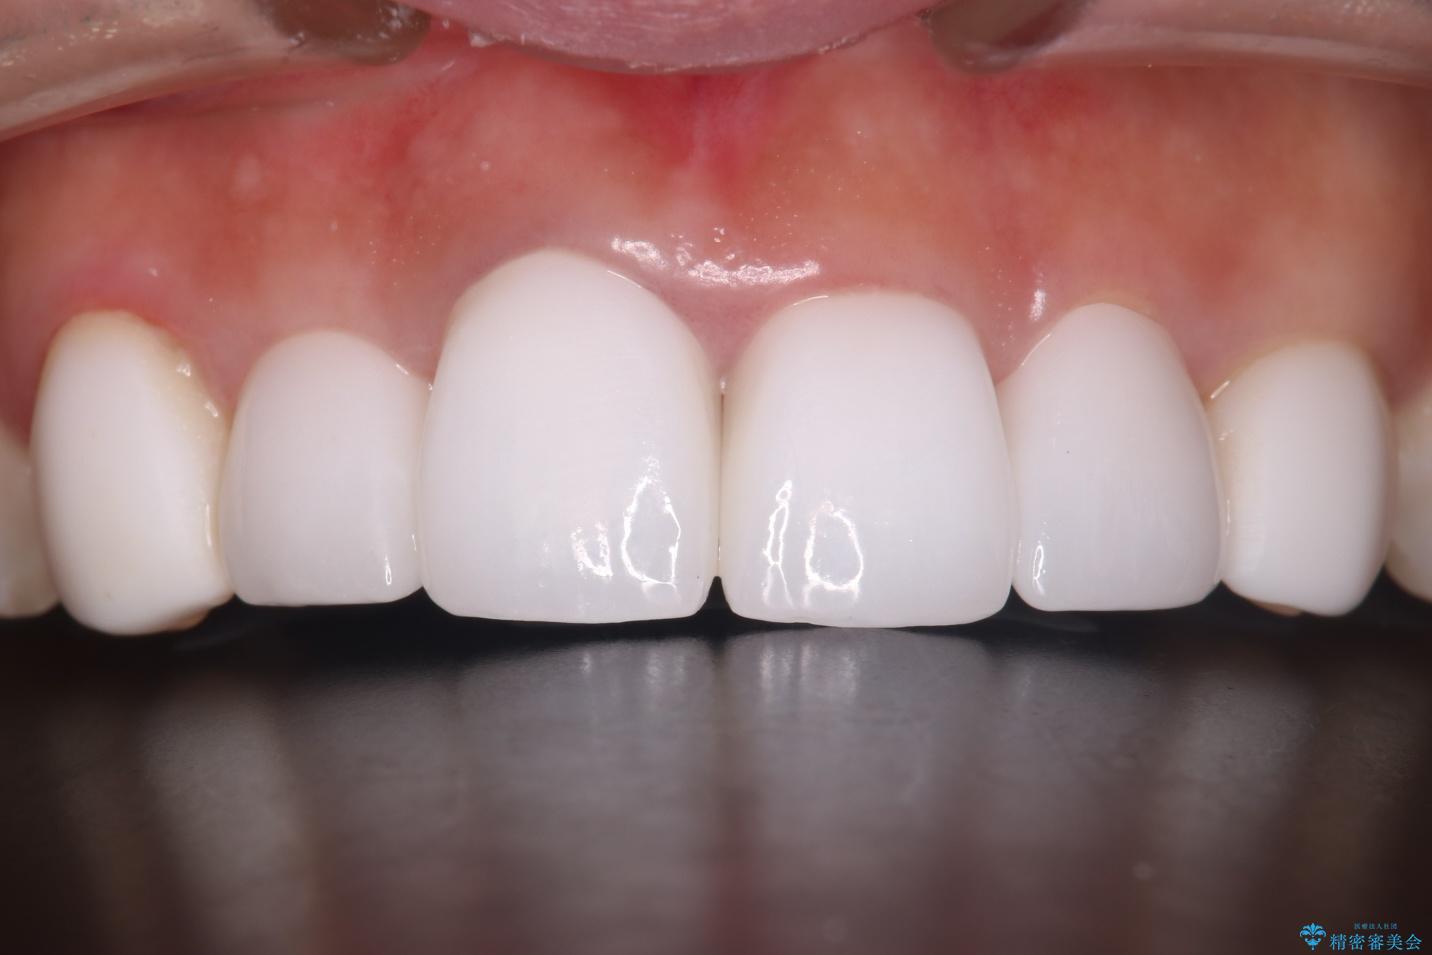

清掃性も上がったおかげで、歯肉の状態も良好に保てています。

色の調和もとれ、患者様には大変ご満足いただけました。